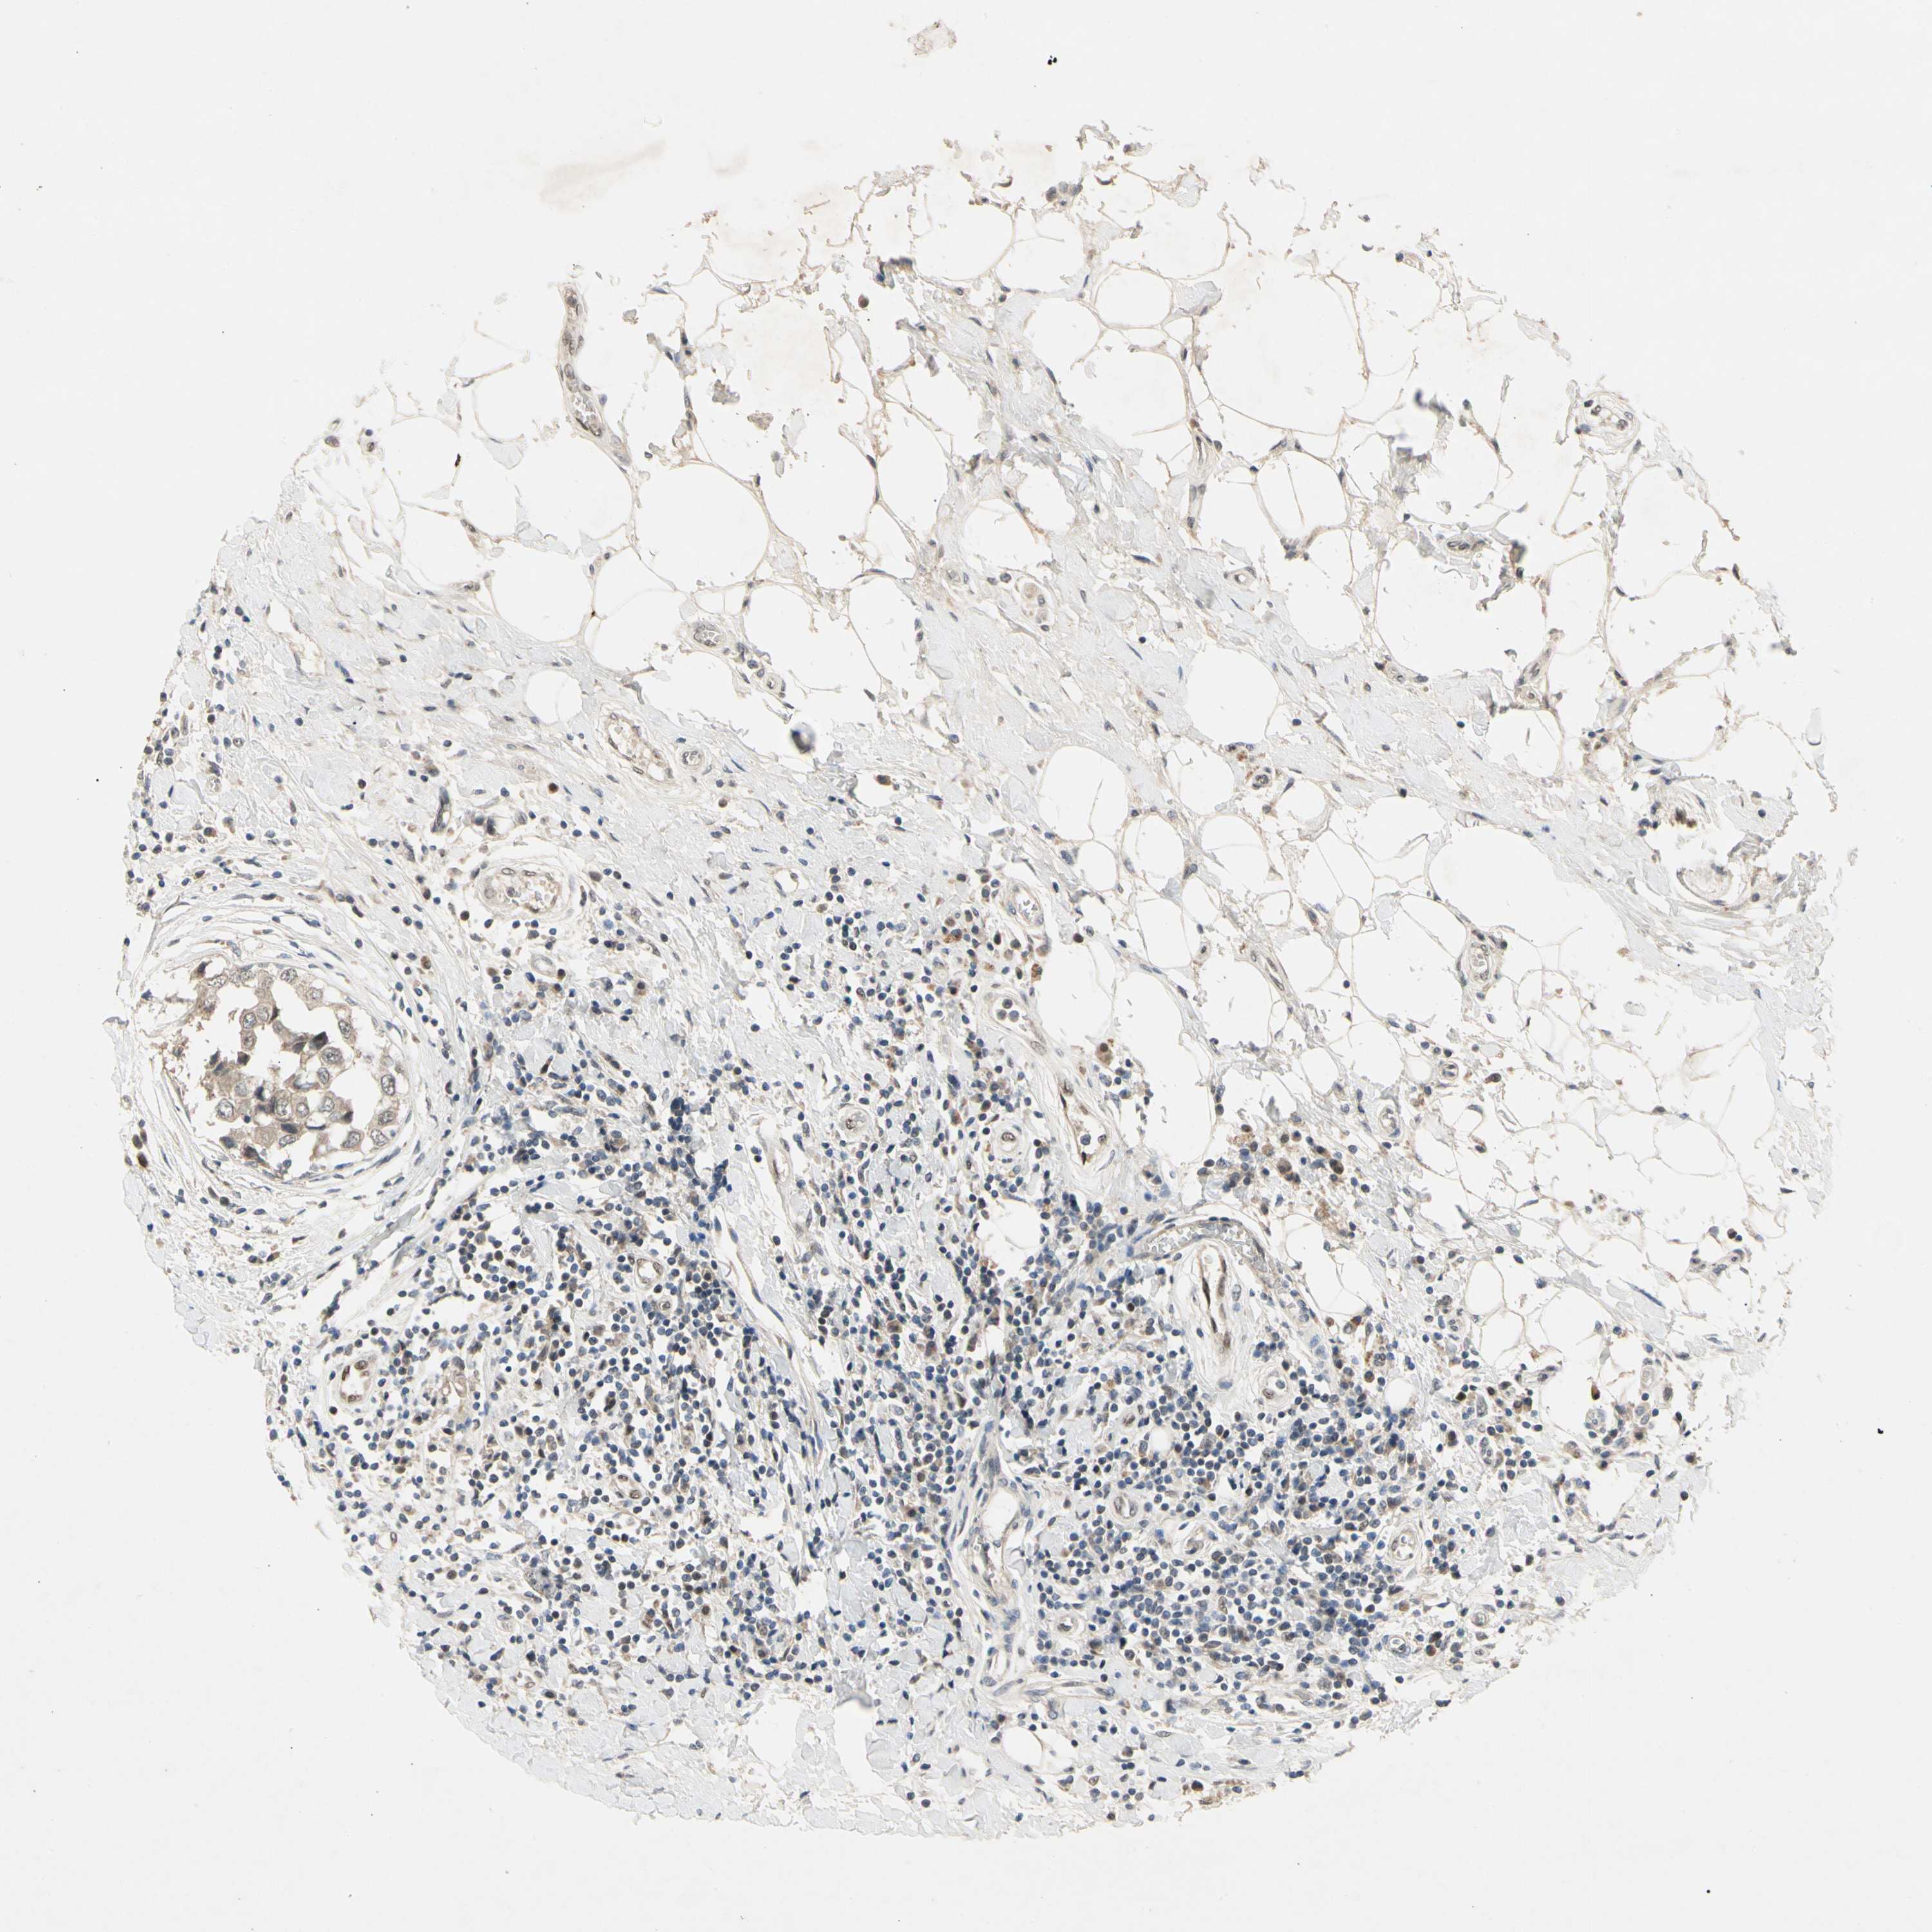

BRCA TCGA BRCA VALIDATION PROTEIN EXPRESSION